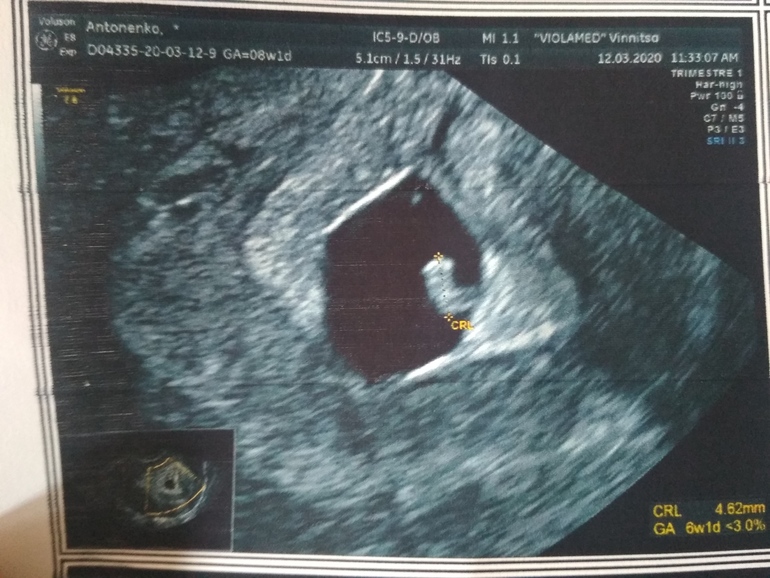

Подтверждение ЗБ